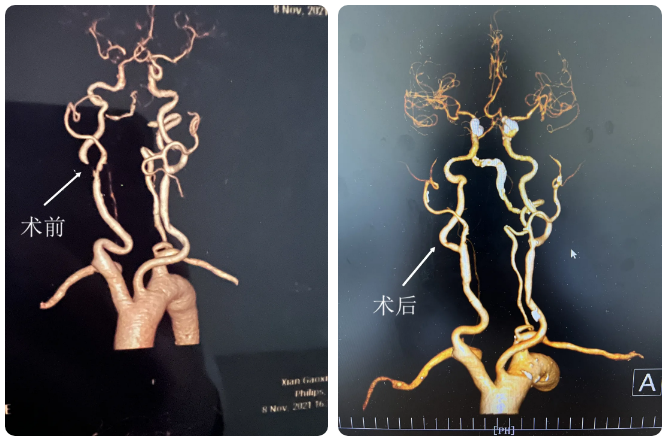

入院后,随着磁共振血管造影(MRA)、CT 血管造影(CTA)、CT 灌注扫描(CTP)及颈部超声(TCD)等各项检查的不断完善,慧奶奶颈内血管狭窄程度以及右侧循环情况逐渐明晰。慧奶奶也从神经内三科转入神经外科,接受进一步治疗。

此时,有三个棘手的难题摆到医生面前。首先,慧奶奶右侧颈动脉狭窄 90%,这意味着她随时可能因为新发的斑块脱落造成致命性的脑梗死;其次,慧奶奶患有双下肢动脉硬化闭塞症,颈部血管迂曲,无法建立手术通路,致使无法实施介入取栓,展开后续治疗;最后,因慧奶奶常年同时服用阿司匹林和氯吡格雷两种药物,手术前需要暂停服用氯吡格雷一周才能进行手术。

目前,慧奶奶已拔除气管插管,术后复查右侧颈动脉通畅,已转入普通病房稳步恢复中。